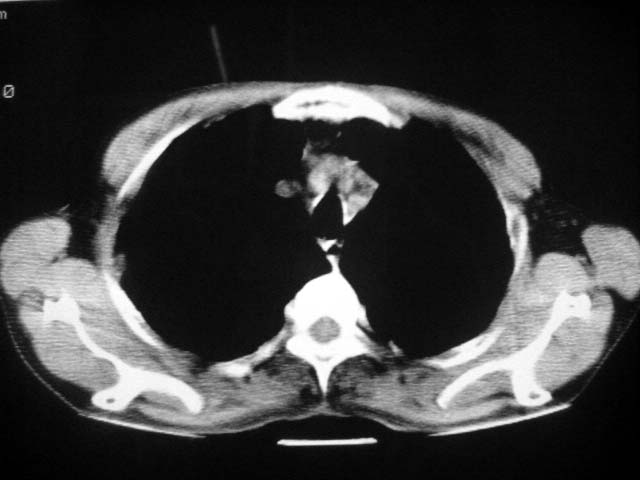

以下是引用zjzjr在2007-9-4 17:00:00的发言:[br]双上肺继发型结核伴左上肺空洞形成.慢性支气管炎伴肺气肿.

以下是引用liuzheng_9326在2007-9-4 16:23:00的发言:[br]痰检未见结核菌, 治疗后症状好转。图像符合陈旧性结核伴感染。